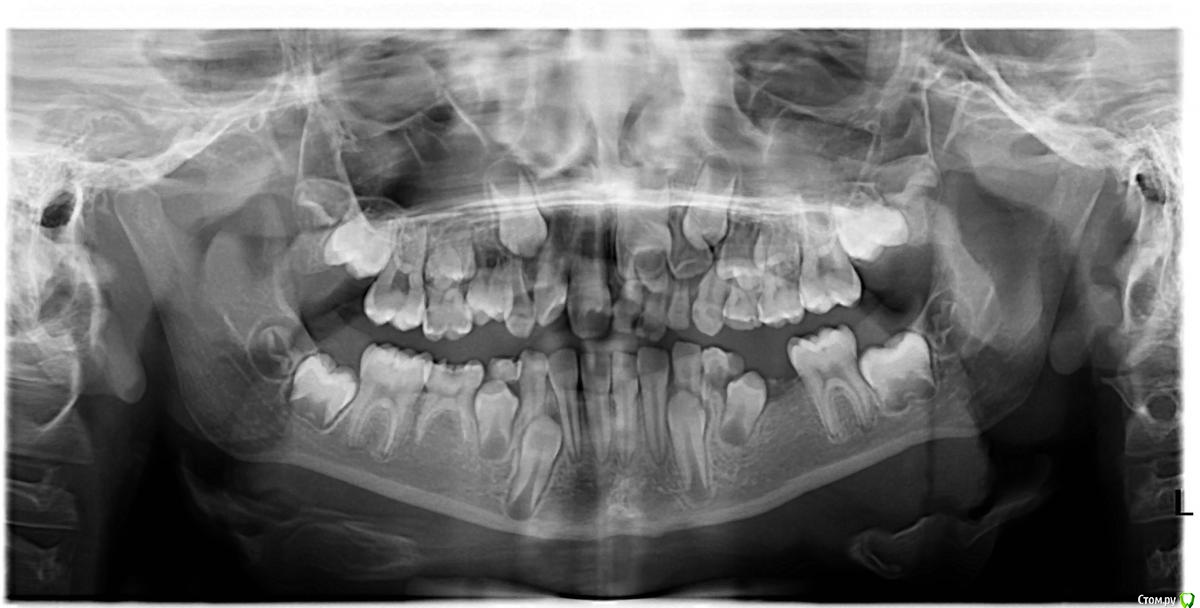

Jeniaspb Опубликовано 18 декабря, 2015 Поделиться Опубликовано 18 декабря, 2015 Кто, что посоветует? Пару слов о самом ребенке: очень и очень неконтактная девочка с очень и очень противной мамашей, но помочь хочется.Скину только орто, вопрос следующий: снизу все более-менее понятно, интересует область резцов слева. У нее 3 молочных резца с левой стороны, плюс по КТ смотрел, прямо за 2.1 нечто похожее на еще один молочный зубец. Стоит ли удалять все три молочных резца и помогать постоянному или дать ему время для прорыва?) З. Ы. : С огромным трудом снимали оттиски, на серьезный аппарат ребенок точно не готов, по ТРГ нижняя микро и вертик тип роста, есть ли смысл пытаться с lm активатором? Ссылка на комментарий

Yana guapa Опубликовано 18 декабря, 2015 Поделиться Опубликовано 18 декабря, 2015 http://i10.pixs.ru/storage/5/1/4/post307090_2235695_19924514.jpg Я бы вот эти все убрала. 1 Ссылка на комментарий

Танья Опубликовано 8 февраля, 2016 Поделиться Опубликовано 8 февраля, 2016 Здравствуйте, коллеги!Я бы ещё планировала удалить 74- чтоб нормально прорезался 34. Есть шанс, что 36 при прорезывании 37 сместится медиально и можно будет обойтись без протезирования. У меня такой опыт был .На в/ч ещё бы удалила соседний молочный слева ( оставив только молочный клык, чтоб держал 24). Учитывая, что справа стоят и 11 и 12-22 тоже пора было бы прорезаться .Главное- все направления грамотно написать и чтоб мама подписывалась , если она не очень корректная) Ссылка на комментарий